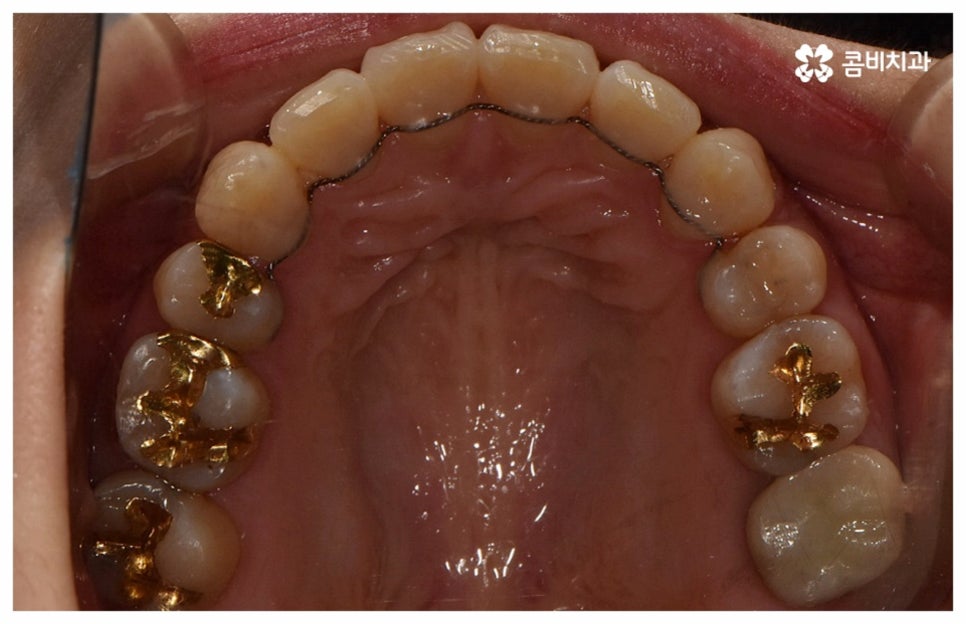

위 사진은 환자분의 동의를 받아 이해를 돕기 위한

사진이며, 실제 치료 결과는 다를 수 있습니다.